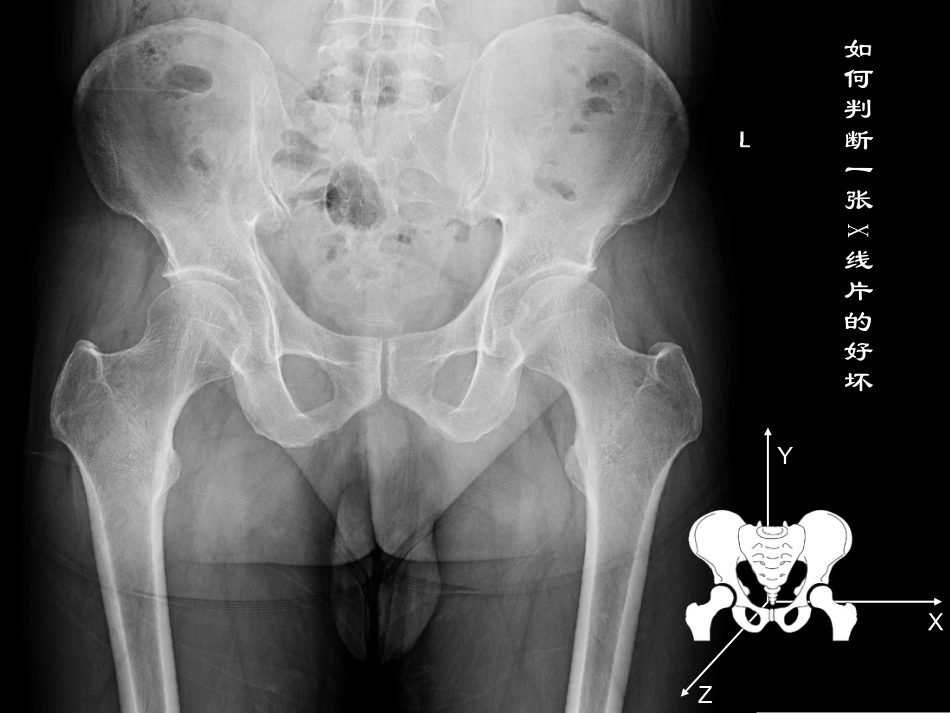

成人发育性髋关节发育不良影像学表现如何判断一张X线片的好坏XYZ骨盆沿X轴方向旋转XYZXYZ骨盆沿X轴方向旋转骨盆沿Y轴方向旋转XYZ骨盆沿X轴方向旋转骨盆沿Z轴方向旋转髋关节常用指标的测量•沈通线与髂颈线•外侧CE角•臼顶倾斜角•髋臼覆盖率•颈干角•夏普角•前CE角•股骨颈前倾角沈通线髂颈线Shenton线:又称耻颈线,为股骨颈内缘与闭孔上缘之间的连线,正常为连续的弧形,如不连续说明髋关节有不同程度的半脱位。Calve线:又称髂颈线,为髂骨外缘与股骨颈外缘光滑的弧线,如不连续说明髋关节有不同程度的半脱位。外侧CE角正常>25°Wiberg外侧CE角:异常的外侧CE角是诊断髋关节发育不良的标准之一,用来评估骨性髋臼在股骨头上方及外侧的覆盖,正常值均大于25°,20~25°为临界值,小于20°则可诊断为髋关节发育外侧CE角发育不良<20°臼顶倾斜角正常<10°被用来评价冠状位上髋臼顶的方向,以及股骨头外上方的覆盖,髋臼的关节承重面在X线片上表现为外形类似“眉弓”的硬化带,正常角度在0~10°之间,髋关节发育不良通常大于10°臼顶倾斜角发育不良>10°髋臼覆盖率正常>0.75指股骨头被骨性髋臼覆盖的百分比,即股骨头内缘至髋臼外缘的距离与股骨头内外缘之间距离的百分比,小于75%为病理性髋臼发育不良。髋臼覆盖率发育不良≤0.75夏普角正常33°-38°Sharp角:观察髋臼的倾斜程度,即髋臼外缘与泪滴下缘之间的连线与骨盆水平线之间的夹角,正常小于40°夏普角发育不良>40°颈干角正常110°-140°股骨颈长轴与股骨干纵轴之间的角度,又称内倾角。大于正常值为髋外翻,小于正常值为髋内翻。髋关节65°斜位示意图夹角25°髋关节65°斜位片:是骨盆真正的侧位片,评估髋臼的前覆盖,有些患者在骨盆正位片上股骨头覆盖正常,在该片上发现前覆盖缺损。体位要求患者站立,骨盆相对于底片旋转65°前CE角正常>25°前CE角发育不良<20°LequenseFalseProfileLequenseFalseProfile位位XX线片的体位要求线片的体位要求患者站立(髋关节应力位像),骨盆相对于患者站立(髋关节应力位像),骨盆相对于底片旋转底片旋转65°65°,与患髋同侧的脚应与底片平,与患髋同侧的脚应与底片平行。行。XX线管距胶片线管距胶片102cm102cm,十字瞄准器对准,十字瞄准器对准患侧股骨头。但应同时投照双侧髋关节,以患侧股骨头。但应同时投照双侧髋关节,以便判断拍照方法是否正确。在拍摄正确的便判断拍照方法是否正确。在拍摄正确的XX线片上,左右两侧股骨头之间的距离应等于线片上,左右两侧股骨头之间的距离应等于11至至22个股骨头的直径。小转子应模糊不清,个股骨头的直径。小转子应模糊不清,表现为股骨干皮质后方的圆形影。小转子过表现为股骨干皮质后方的圆形影。小转子过于明显则提示下肢内旋。于明显则提示下肢内旋。前倾角=34.5°+23.8°=58.3°前倾角正常12-15°•髋关节外展前后位片拍该片的目的在于:评估如果选择髋臼截骨,可以判断髋臼重新转位之后股骨与髋关节的对合关系,或选择做股骨粗隆间截骨来改善头臼对合关系谢谢!